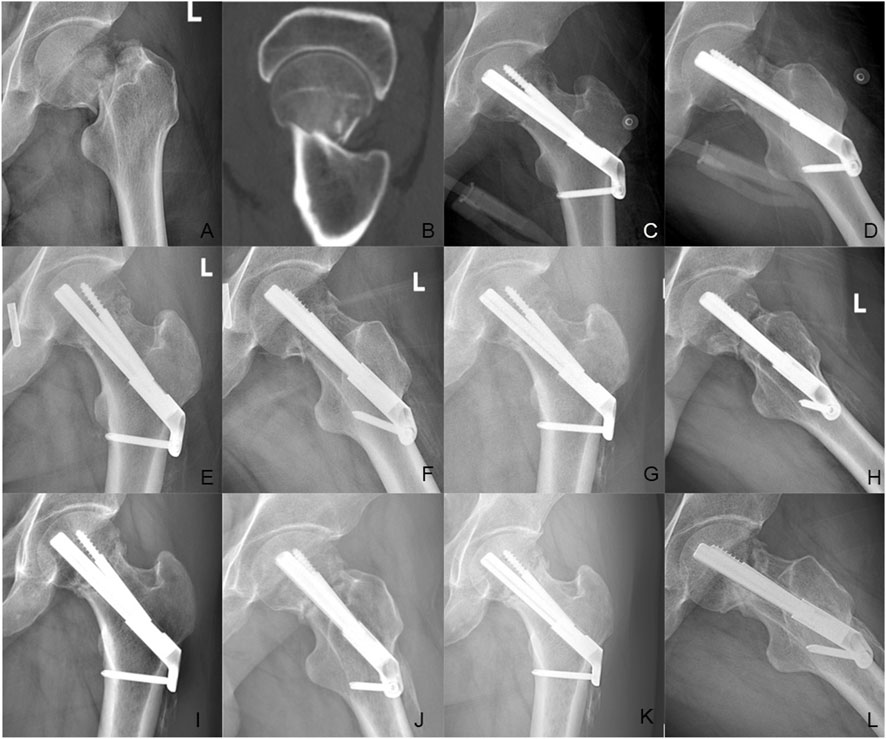

Background The purpose of this study was to explore the biomechanical property and clinical efficacy of femoral neck system (FNS) with an additional cannulated screws (CS) in the treatment of unstable femoral neck fracture (FNFs) with comminuted posteromedial cortex. Methods Firstly, we developed a model of Pauwels type III FNF with comminuted posteromedial cortex for the finite element analysis (FEA). Two experimental models were set up: the FNS model and the FNS+CS model. The von Mises stress on the proximal femur, implant and the total displacement of the device components were evaluated for both FNS and FNS+CS models. Secondly, we retrospectively included the cases of vertical FNFs with comminuted posteromedial cortex by FNS or FNS+CS fixation in our hospital from January 2020 to December 2023. In this study, demographic information, femoral neck shortening, Harris score of hip joint function, and postoperative complications were collected and compared. Results The FEA results showed similar peak von Mises stress of the implant in two models and the additional CS could share the stress concentration with the FNS in the FNS+CS model. In terms of proximal femur, the maximum von Mises stress of the FNS model increased by 15.43% when compared with the FNS+CS model, and the magnitude of these two models were 83.02MPa and 71.92 MPa, respectively. Furthermore, the maximum displacement in the FNS+CS model was much smaller than that in the FNS model. Clinically, the femoral neck shortening distance was significantly longer in the FNS group (5.62±3.32 mm) than that in the FNS+CS group (3.49±2.01 mm) (p = 0.027). Furthermore, the incidence of moderate to severe shortening (≥ 5 mm) was significantly higher in the FNS group compared with the FNS+CS group (p = 0.039). Moreover, the patients in the FNS+CS group had a higher Harris score than patients in the FNS group (91.97 vs. 88.56, p = 0.003). Conclusions Compared to the FNS alone, the FEA results showed that the FNS+CS had better biomechanical properties and the clinical results showed that the FNS+CS had a shorter femoral neck shortening and higher Harris score in treating unstable FNFs with comminuted posteromedial cortex.